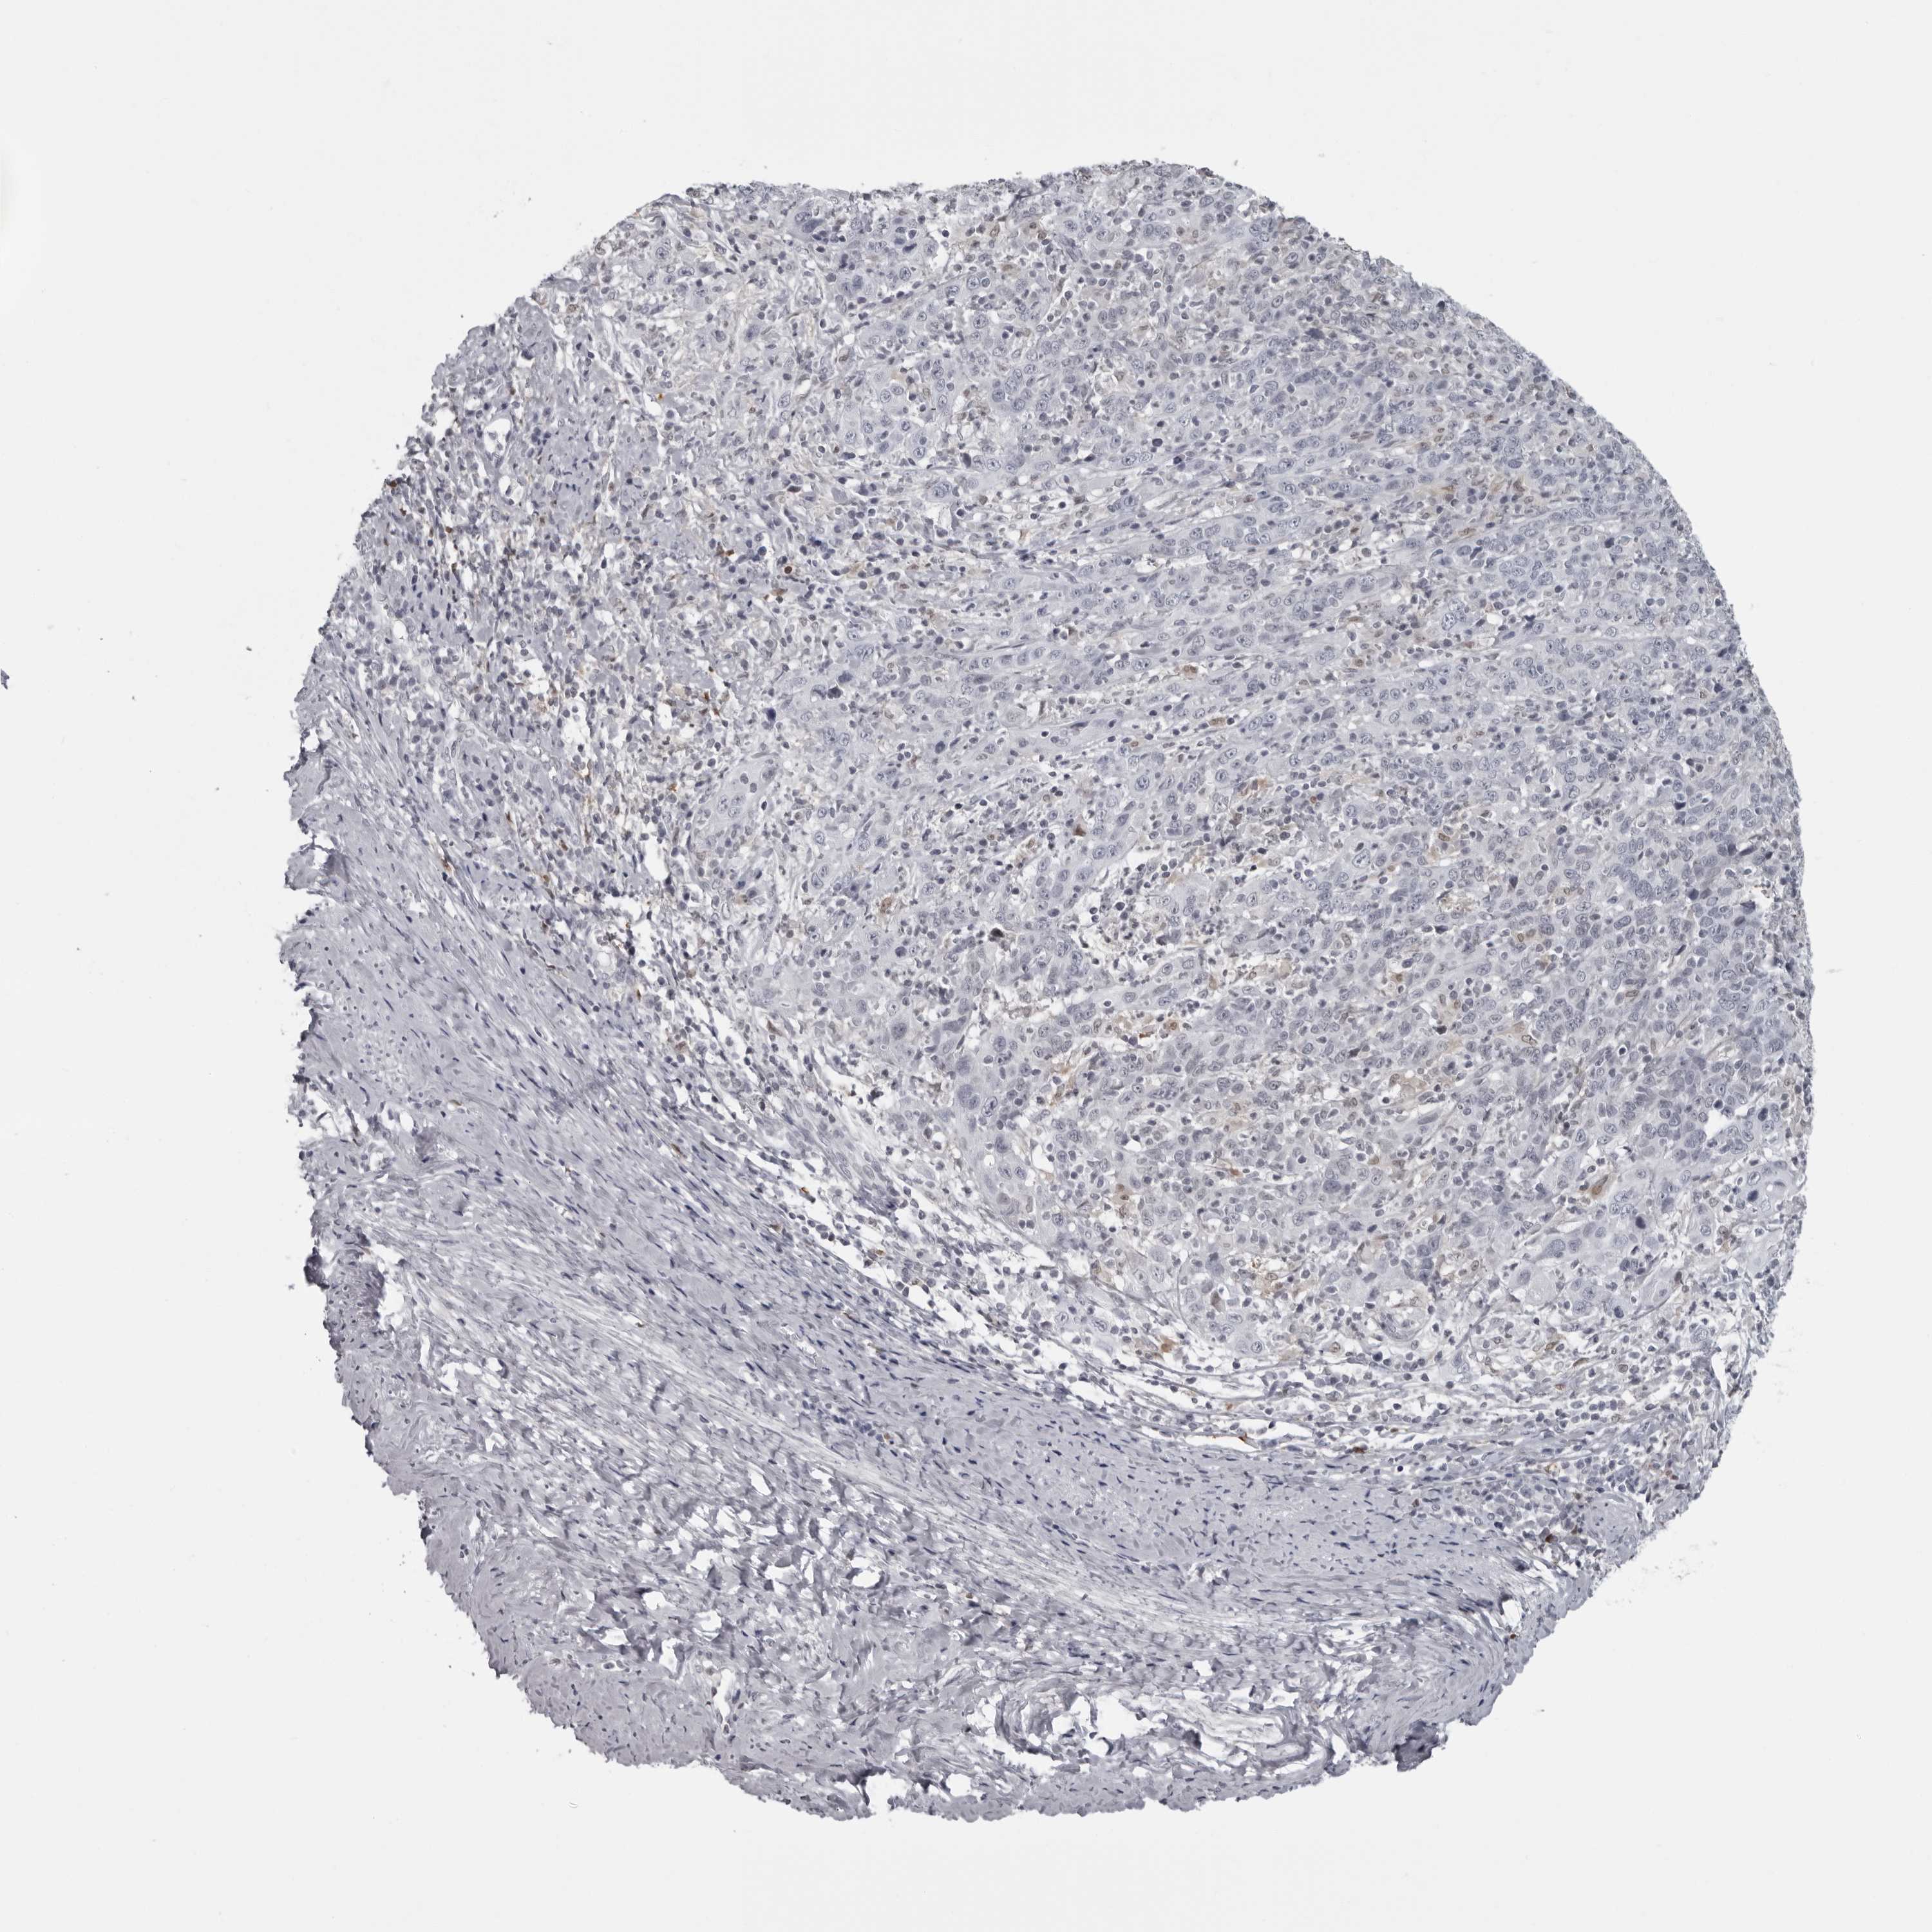

CERVICAL CANCER - Protein expressioni

A mouse-over function shows sample information and annotation data. Click on an image to view it in a full screen mode. Samples can be filtered based on level of antibody staining by selecting one or several of the following categories: high, medium, low and not detected. The assay and annotation is described here.

Note that samples used for immunohistochemistry by the Human Protein Atlas do not correspond to samples in the TCGA dataset.

Antibody stainingi

Antibody staining in the annotated cell types in the current human tissue is reported as not detected, low, medium, or high, based on conventional immunohistochemistry profiling in selected tissues. This score is based on the combination of the staining intensity and fraction of stained cells.

Each image is clickable and will lead to virtual microscopy that enables deeper exploration of all samples and also displays staining intensity scores, fraction scores and subcellular localization as well as patient and tissue information for each sample.

Antibody HPA028184

Staining

High

Medium

Low

Not detected

Intensity

Strong

Moderate

Weak

Negative

Quantity

>75%

75%-25%

<25%

None

Location

Nuclear

Cytoplasmic/membranous

Cytoplasmic/membranous,nuclear

Squamous cell carcinoma, NOS

Adenocarcinoma, NOS